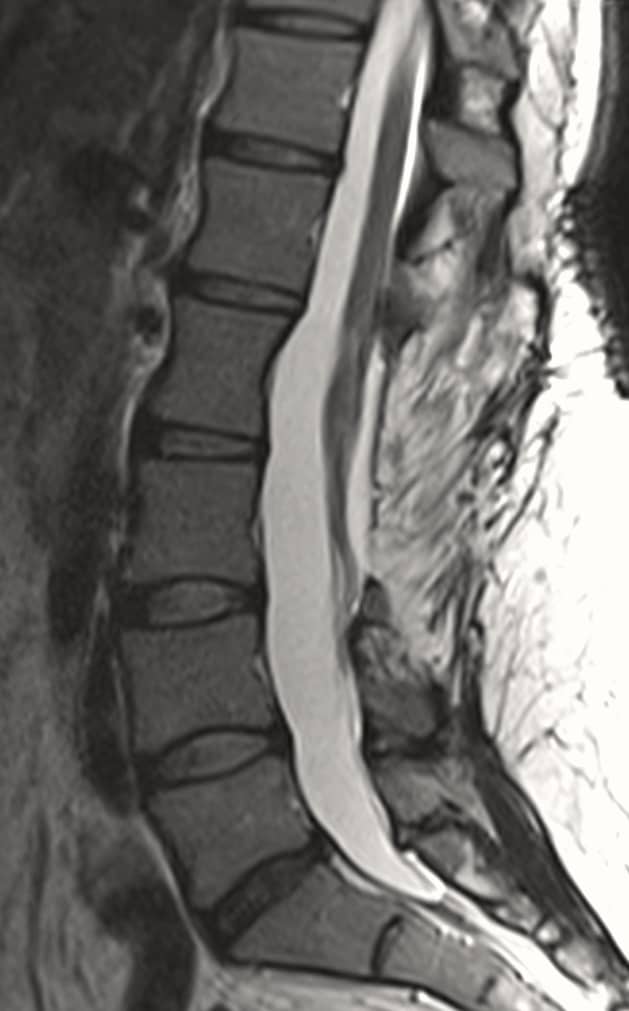

MRI of lumbar spine shows large dermoid tumor in the spinal canal putting severe pressure on the spinal cord and nerve roots.